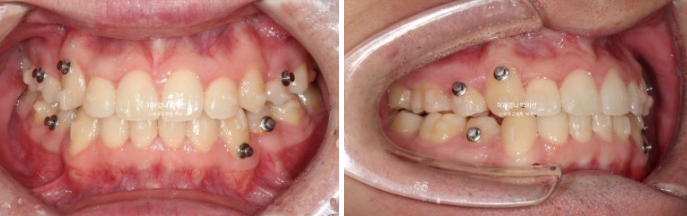

2022.09

송곳니 덧니가 심합니다. high canine 하이캐나인 이라고 합니다.

덧니가 심해서 작은어금니 4개 발치가 불가피한 상황입니다.

약간의 입술돌출도 함께 해소하기로 했습니다.

인비절라인으로 치료 시작했으며 장치제작기간을 한달 반을 기다려 10월부터 인비절라인 1번 장치를 끼기 시작했습니다.